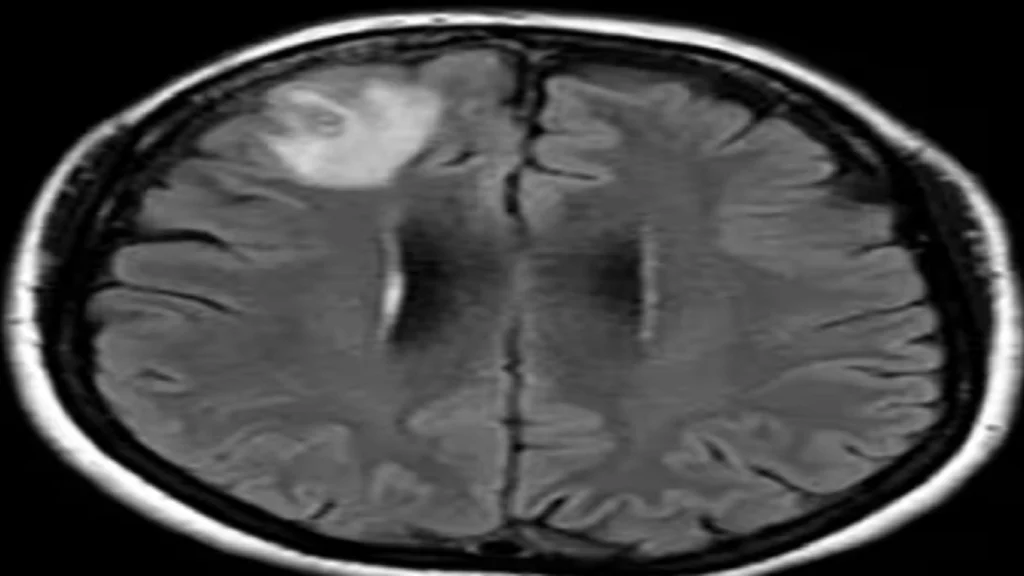

Patienten, en 64-årig kvinde fra det sydøstlige New South Wales, blev oprindeligt indlagt på hendes lokale hospital i slutningen af januar 2021 med tre uger med mavesmerter og diarré, efterfulgt af vedvarende hoste, feber og nattesved i 2022. Hendes symptomer inkluderede også glemsomhed og depression, hvilket førte til en henvisning til Canberra Hospital. En MR-scanning af hendes hjerne afslørede uforklarlige abnormiteter, der krævede kirurgisk indgreb.

Det, der kom som en overraskelse, var, at under operationen trak neurokirurgen en 8 cm lang parasitisk rundorm ud fra patientens hjerne. Dr. Bandi var i chok og ringede straks til Dr. Senanayake og andre kolleger for at søge rådgivning om, hvordan man skulle håndtere denne utrolige situation.